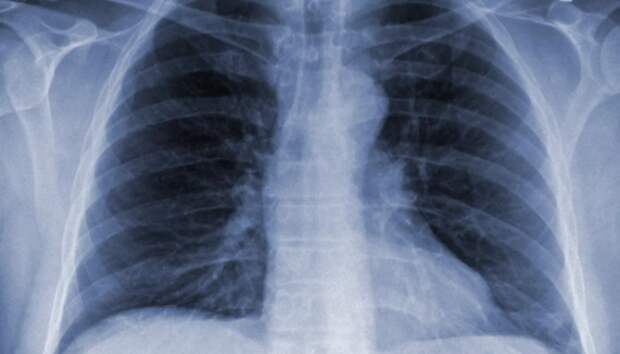

Всем пациентам с воспалением легких неоднократно проводится исследование на COVID-19 Шесть человек за сутки госпитализированы с внебольничной пневмонией в Карелии, сообщает оперштаб по борьбе с распространением коронавирусной инфекции. Летальных исходов не зарегистрировано. Начиная с 1 апреля, с внебольничной пневмонией госпитализированы 1222 пациента, 74 человека умерли (с учетом пациентов, госпитализированных ранее указанного периода).